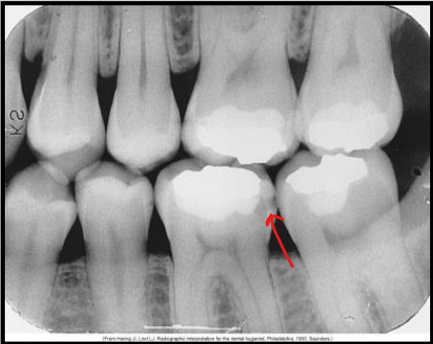

What class of interproximal caries is this?

Class 2 - Moderate